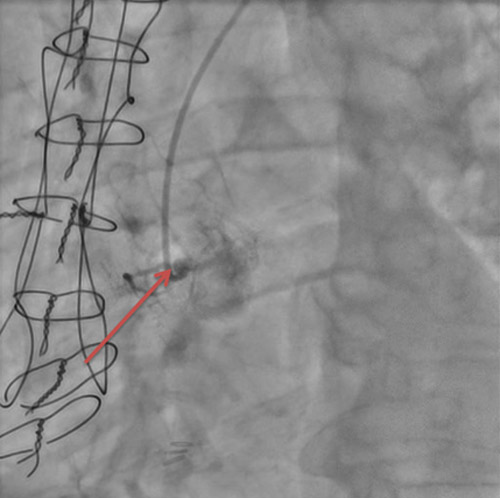

Il existait un doute sur une sténose à l’ostium de la mammaire interne gauche, avec un rétrécissement estimé visuellement à 50%, avec une légère ventricularisation des pressions lors de l’intubation sélective.

Images 5 : sténose intermédiaire de l’ostium de la mammaire interne gauche

Nous avons discuté du dossier de la patiente avec notre équipe, et avons décidé de documenter une ischémie avant d’envisager une angioplastie de l’ostium de cette mammaire interne gauche.

En effet, la désocclusion du réseau natif semble très complexe, et l’angioplastie de la mammaire nous semblait risquée, étant donné la fragilité des ostia mammaires, et également le fait que ce pont était son dernier vaisseau restant, le réseau natif étant subocclus.

Il a été convenu qu’en cas de large ischémie, nous envisagerions une angioplastie de l’ostium de cette mammaire interne gauche.